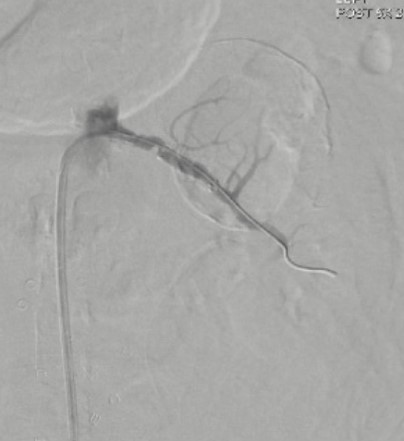

The facility’s ruptured aneurysm protocol was activated, and the patient was taken immediately to the hybrid operating room. Given the patient’s underlying COPD and previous abdominal surgery with mesh, a decision was made to proceed with endovascular intervention. The right common femoral artery was accessed with ultrasound guidance and a micropuncture kit. After exchanging for a Bentson wire (Cook Medical) and a 5F sheath, a VS2 catheter (Gore Medical) was used to engage and selectively image the left renal artery. With selective imaging, we were pleasantly surprised to see an adequate amount of renal artery distal to the aneurysm neck, allowing for placement of a covered stent (Figure 2).